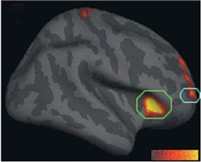

Acima: Regiões corticais mais espessas em pessoas que meditam aparecem em ambos os hemisférios cerebrais. Este mapa estatístico ilustra esta intensidade em cada ponto da superfície cortical.

Adicionalmente, a meditação pode retardar a diminuição do córtex frontal causada pelo envelhecimento do indivíduo.  Os gráficos ao lado mostram a média da espessura cortical de cada participante em duas regiões distintas do cérebro em relação às suas idades. Os participantes que meditavam estão representados pelos pontos azuis enquanto aqueles do grupo de controle estão representados pelos pontos vermelhos. Repare que os participantes que meditavam mantêm a sua espessura cortical ao longo da vida, enquanto aqueles que não meditam sofrem um decréscimo nestas regiões.